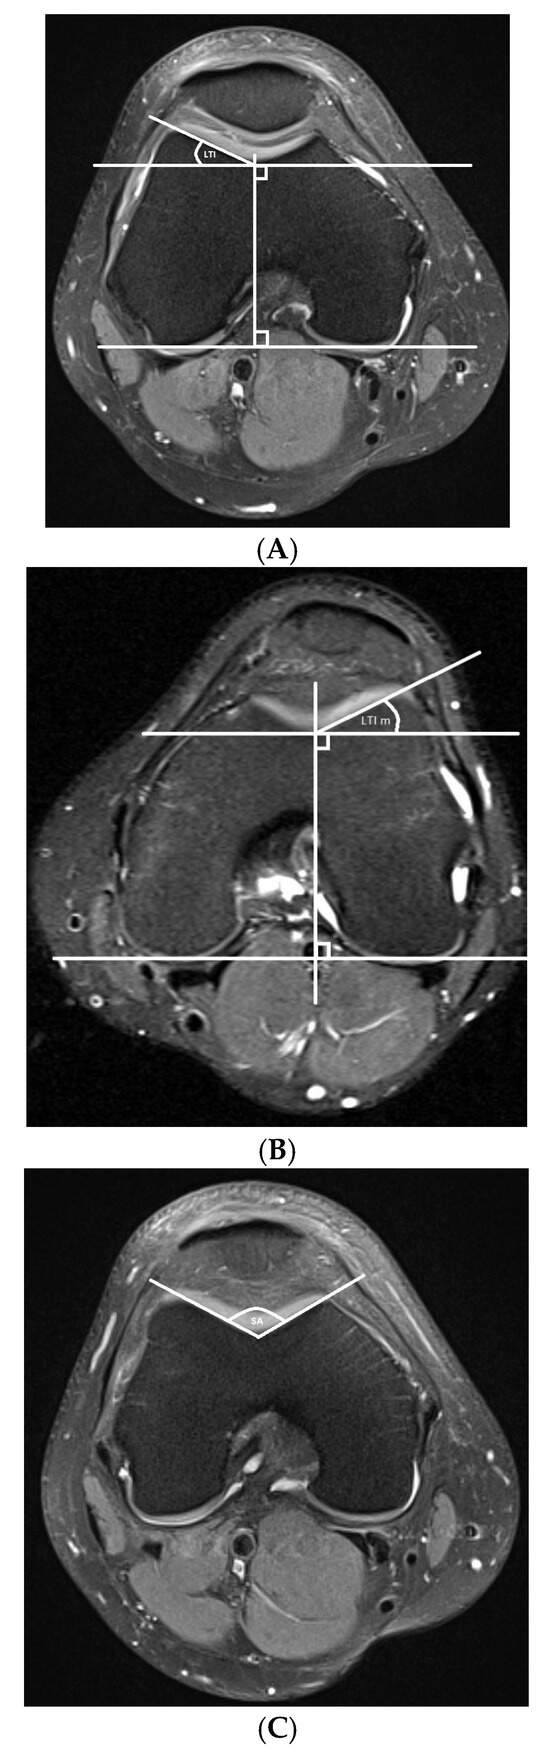

- Trochlear dysplasia measurements

- Lateralization measurements